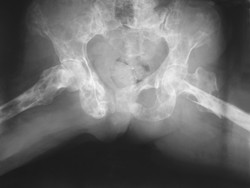

Szpiczak mnogi jest nowotworem złośliwym krwi, zlokalizowanym w szpiku kostnym. Współczesne metody leczenia muszą uwzględniać wpływ mikrośrodowiska, jakie tworzy szpik kostny.

Dwie trzecie przypadków szpiczaka mnogiego stwierdza się u pacjentów w podeszłym wieki i niemal zawsze są one nieuleczalne. Guz ten tworzy się z dojrzałych, wytwarzających przeciwciała limfocytów B, które rozwijają się w niszy szpiku kostnego. Są one otoczone komórkami tkanki kostnej i szpiku kostnego, naczyniami krwionośnymi i komórkami odpornościowymi. Cytokiny w tym mikrośrodowisku pomagają komórkom nowotworowym uniknąć śmierci i nadają im oporność na leki. Patogeneza szpiczaka mnogiego obejmuje nie tylko zmiany genetyczne w obrębie guza, ale również powstanie sprzyjających warunków mikrośrodowiska szpiku kostnego. Celem finansowanego przez UE projektu OPTATIO(odnośnik otworzy się w nowym oknie) (Optimizing targets and therapeutics in high risk and refractory multiple myeloma) było zbadanie głównych elementów tego układu wspierającego nowotwór. W projekcie OPTATIO stworzono repozytorium danych z rejestrów i biobanków wirtualnych, aby zidentyfikować biomarkery oporności. Scharakteryzowano szereg markerów, w tym dwa związane z opornością na bortezomib, który jest głównym lekiem na szpiczaka mnogiego. Analiza danych klinicznych pozwoliła skorelować występowanie określonych interakcji szpiczaka mnogiego z jego mikrośrodowiskiem z patogenezą nowotworu i jego opornością na leczenie w modelach in vitro i in vivo. Dane te poddano walidacji w oznaczeniach jednoczesnych kultur autologicznych szpiczaka mnogiego i komórek z jego mikrośrodowiska. Modele zostały też wykorzystane do opracowania związków wiodących leków skierowanych przeciwko komórkom szpiczaka mnogiego w kontekście jego mikrośrodowiska. Aby móc prowadzić badania przesiewowe skuteczności leków, opracowano mysie modele do nieinwazyjnego obrazowania szpiczaka mnogiego i zdrowej tkanki immunologicznej. W tej technice korzystano w wielokolorowej mikroskopii fluorescencyjnej warstw światła (LSFM) i stworzono modele ksenogennego szpiczaka mnogiego z komórek nowotworowych pobranych od ludzi, aby prowadzić nieinwazyjne obrazowanie bioluminescencyjne całego ciała. Odkryto dwa związki silniej zwalczające szpiczaka niż bortezomib. Ponadto niektóre z badanych związków wpływały na mikrośrodowisko związane z tym nowotworem. Po przetestowaniu na błonie kosmówkowo-omoczniowej zarodka kurzego stwierdzono, że znacząco hamowały wywołaną szpiczakiem mnogim neoangiogenezę w pobliżu ksenograftu oraz, nawet w niewielkich ilościach, ograniczały ponowne unaczynienie. Informacje o postępach projektu OPTATIO były przekazywane podczas spotkań naukowych i konferencji specjalistycznych. Wyniki doświadczeń przełożyły się na 31 publikacji naukowych. Oczekiwany wpływ projektu obejmuje ulepszenie diagnostyki i metod prowadzenia badań przesiewowych leków oraz stworzenie bardziej skutecznej, spersonalizowanej terapii dla chorych na szpiczaka mnogiego.